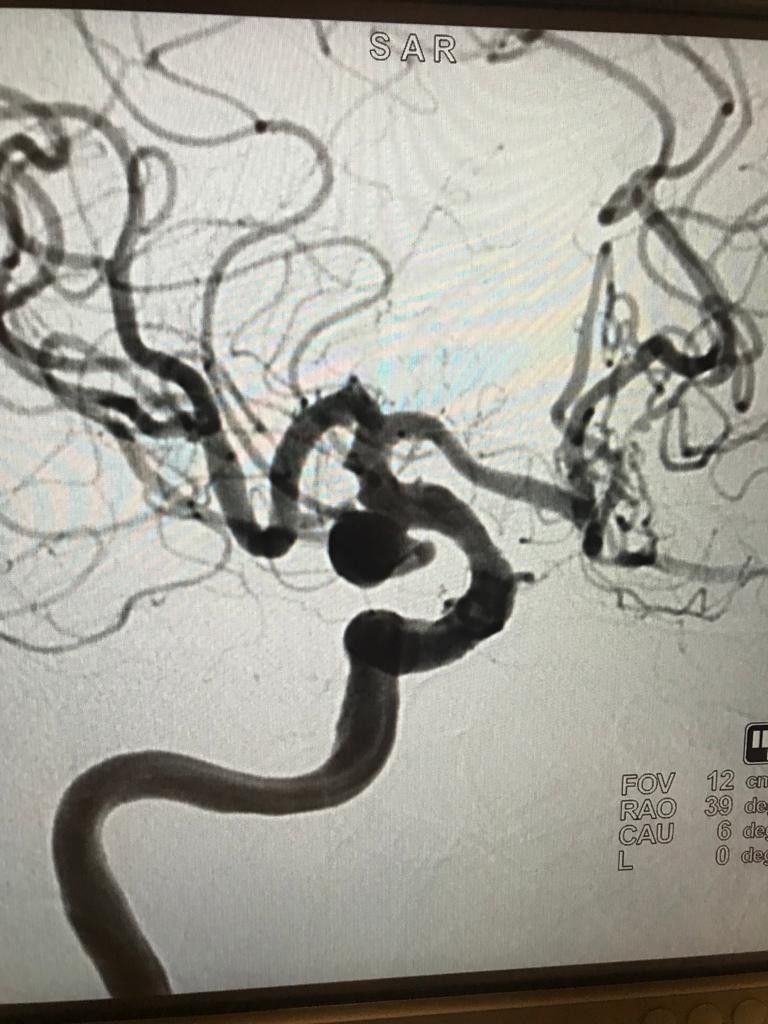

Balıkesir'in Ayvalık ilçesinde yaşayan Sonsen Küçük (75), son zamanlarda dengesizlik, baş ağrısı, ellerde uyuşma ve uyuklama gibi sorunlar yaşamaya başladı. Hipertansiyon ve diyabet hastalıklarına sahip olan Küçük'ün, Medicana International İzmir Hastanesinde yapılan tetkiklerin ardından beyni besleyen arkadaki 2 damarın ve öndeki 1 şah damarının tamamen kapalı olduğu ortaya çıktı.

Sonsen Küçük'ün, onu hayata bağlayan öndeki tek şah damarında da baloncuk meydana geldiği, beyin kanaması geçirme riskinin çok büyük olduğu ortaya çıktı. Hastayı hızlı bir şekilde operasyona alan Beyin ve Sinir Cerrahisi Uzmanı Doç. Dr. Özhan Merzuk Uçkun, "Sağlıklı insanlarda beyni besleyen 4 damar varken, bu hastadaki 3 damar kapalıydı ve sadece tek damarı beyni beslemeye devam ediyordu. Onda da anevrizma dediğimiz baloncuk meydana gelmişti. Hastanın hipertansiyonu ve diyabeti olduğu için o damarı kurtarmamız gerekiyordu. Bu işlem sırasında damarda meydana gelebilecek hasarlanma ya da kanama hastanın hayatını bitirebilirdi. Kasıktan gerçekleştirdiğimiz operasyonda, stentle anevrizmayı kapattık ve damardaki daralmayı genişlettik" diye konuştu.

Damardaki anevrizmaları saatli bombaya benzeten Doç. Dr. Uçkun, "Bu tür anevrizmaların ne zaman nerede patlayacağı belli olmaz. Her an meydana gelebilir. Özellikle hipertansiyonu olan hastalarda bu risk daha yüksektir. Kafatası açılmadan, kasıktan girilerek gerçekleştirdiğimiz operasyonla hastanın ellerindeki karıncalanma ve uyuklama gibi şikayetleri düzeldi. Hastamızı işlemden 2 gün sonra taburcu ediyoruz. Bu nedenle insanların dengesizlik, baş ağrısı, ellerde uyuşma ve karıncalanma gibi şikayetlere karşı duyarlı olması gerekiyor" dedi.